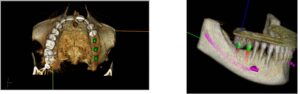

G) PROGETTAZIONE PER MEZZO DEL COMPUTER, CON LA RICOSTRUZIONE DIGITALE IN 3D DI ESAMI RADIOLOGICI E L’UTILIZZO DI MODELLI STEREOLITOGRAFICI.

Questa tecnologia ci permette di progettare e di stabilire a priori l’esatta posizione degli impianti da inserire, fig.45-46 evitare strutture anatomiche pericolose (nervi, arterie, muscoli ecc.) fig.46 di conoscere l’esatta morfologia dell’osso da utilizzare e le sue caratteristiche (densità trabecolatura ecc.);

inoltre ci consente di realizzare con precisione anche la protesi provvisoria immediata fig.47-48 prima dell’inserimento degli impianti. Questo manufatto così si adatterà perfettamente alla posizione dei monconi stabilita prima dell’intervento, in modo virtuale con il software 3D.

Da questo progetto virtuale eseguito sul computer è inoltre possibile realizzare (con l’utilizzo di una stampante 3D) un modello fisico (stereo-litografico) della mandibola o dell’osso mascellare riproducendo fedelmente tutti i dettagli anatomici. Su questo modello simuliamo le estrazioni dentali, le modifiche sull’osso

ed infine l’inserimento degli impianti valutando attentamente di non interferire con strutture anatomiche pericolose adiacenti. Tutto viene programmato e pianificato (misure e angolazioni impianti, innesti ossei, protesi provvisoria ecc.) PRIMA CHE VENGA RIPRODOTTO REALMENTE SULLA PERSONA CON L`INTERVENTO CHIRURGICO IMPLANTARE.

Questo procedimento che attraversa una ‘sì dettagliata fase di programmazione realizzata prima dell’intervento consente di ridurre del 90% il rischio di effetti collaterali e conseguenze impreviste assicurando la riuscita della terapia chirurgica.

Il giorno dell’intervento non bisogna pensare come procedere, ma solo trasferire meccanicamente sul paziente il progetto precedentemente realizzato sul modello anatomico, tutto con serenità, rapidità e sicurezza per la riuscita della terapia chirurgica, garantendo così il risultato.